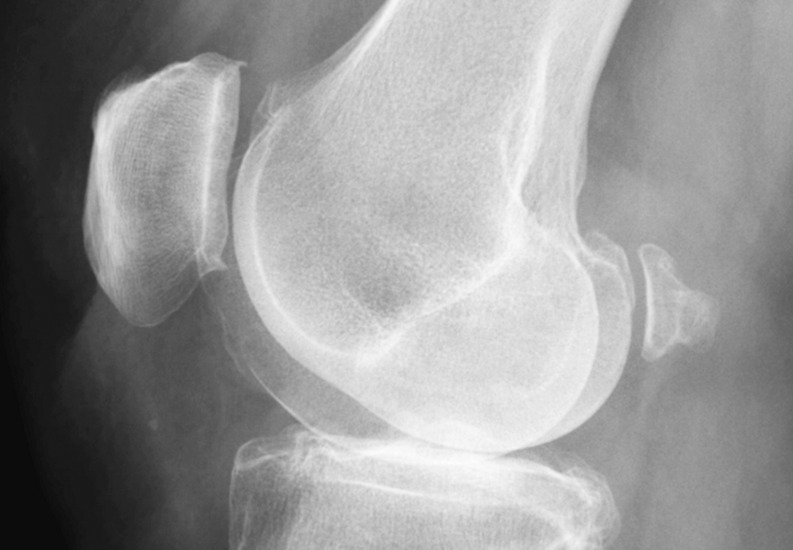

Purpose: The fabella is a sesamoid bone located posterior to the lateral femoral epicondyle within the gastrocnemius muscle. While commonly present in mammals, its prevalence in humans remains unclear, with reported rates ranging from 3 to 87%. Fabella is more frequently observed in Asian and Australian populations but is rare in European and American populations. Although often asymptomatic, it can sometimes cause knee pain, known as "fabella syndrome," and may contribute to neurological symptoms when in proximity to the common fibular nerve. Given the limited awareness of fabella's presence, this study aims to assess its prevalence and anatomical characteristics to aid in the differential diagnosis of knee pain.

Methods: A retrospective analysis was conducted on 500 knee radiographs from 383 patients experiencing knee pain. Data collected included patient age and sex, fabella presence and dimensions, fabella location (distances to surrounding bony structures), patella dimensions, and patellotibial ligament length.

Results: Fabella was detected in 31 females (14.76%) and 29 males (25.66%). Among the examined knees, fabella was present in 40 (12.82%) of female and 39 (20.74%) of male knees. The mean fabella length was 8.85 mm (SD = 2.59), and thickness was 5.63 mm (SD = 1.88), with no significant sex differences. No correlation was found between fabella size and patella dimensions. Notably, patients with fabella were older on average, and bilateral fabellae were significantly larger than unilateral cases (p < 0.05).

Conclusion: Fabella is a relatively common anatomical variant in Central European populations, present in one in six women and one in four men. Its increased prevalence in older individuals suggests a potential age-related development. A comprehensive understanding of fabella anatomy may aid clinicians in diagnosing and managing unexplained knee pain, particularly in elderly patients.